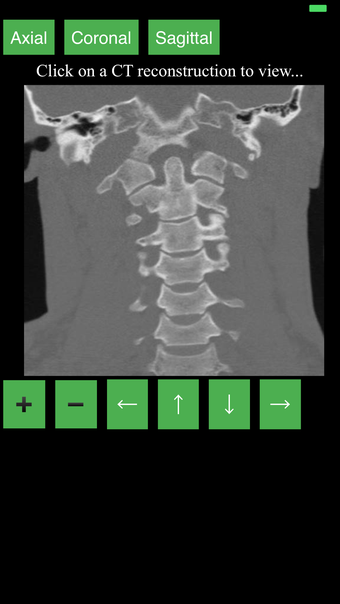

Перекрестные разрезы данных КТ предоставляют динамический и интерактивный метод просмотра поперечной анатомии человека. Вы можете вращать, увеличивать и перемещать изображение, чтобы изучать любую часть тела в деталях.

Перекрестные разрезы создаются с помощью комбинации математических алгоритмов для интерпретации данных из серии сканирований. Результирующие изображения затем преобразуются в серию 2D поперечных срезов и отображаются в специальном приложении для просмотра.